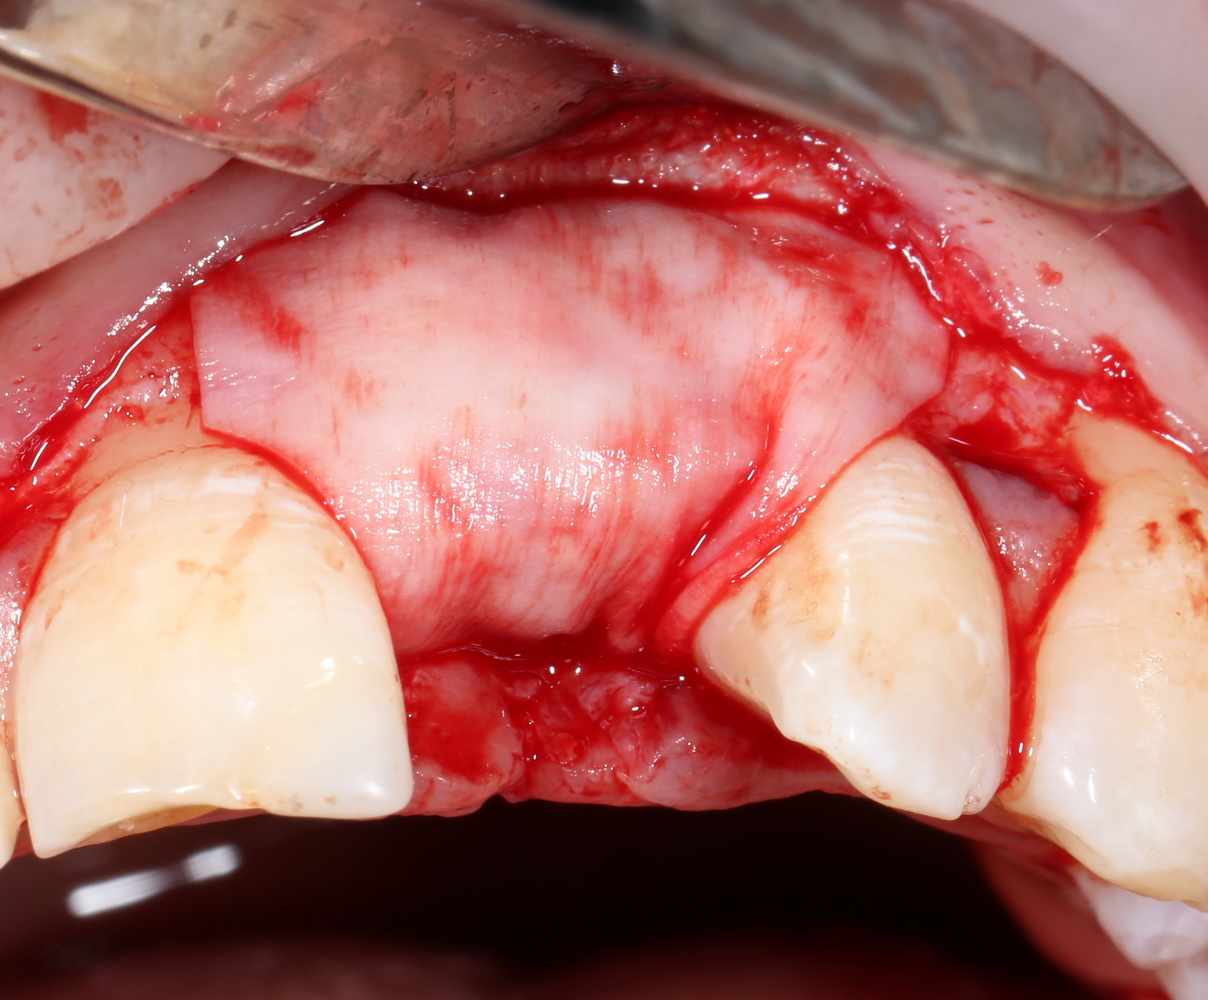

В этом случае остеопластика делается отдельной процедурой. Ее принципы точно те же, но уже без импланта. Например:

Имплантировать в таких условиях — заведомо обрекать себя на хреновый, с точки зрения эстетики и функциональности, результат. Поэтому первым этапом проводим остеопластику. Объем небольшой, использовать в таких объемах костный блок не очень рационально. Воспользуемся аутокостной стружкой и мембраной.

Сначала фиксируется BioGide. Это легко: